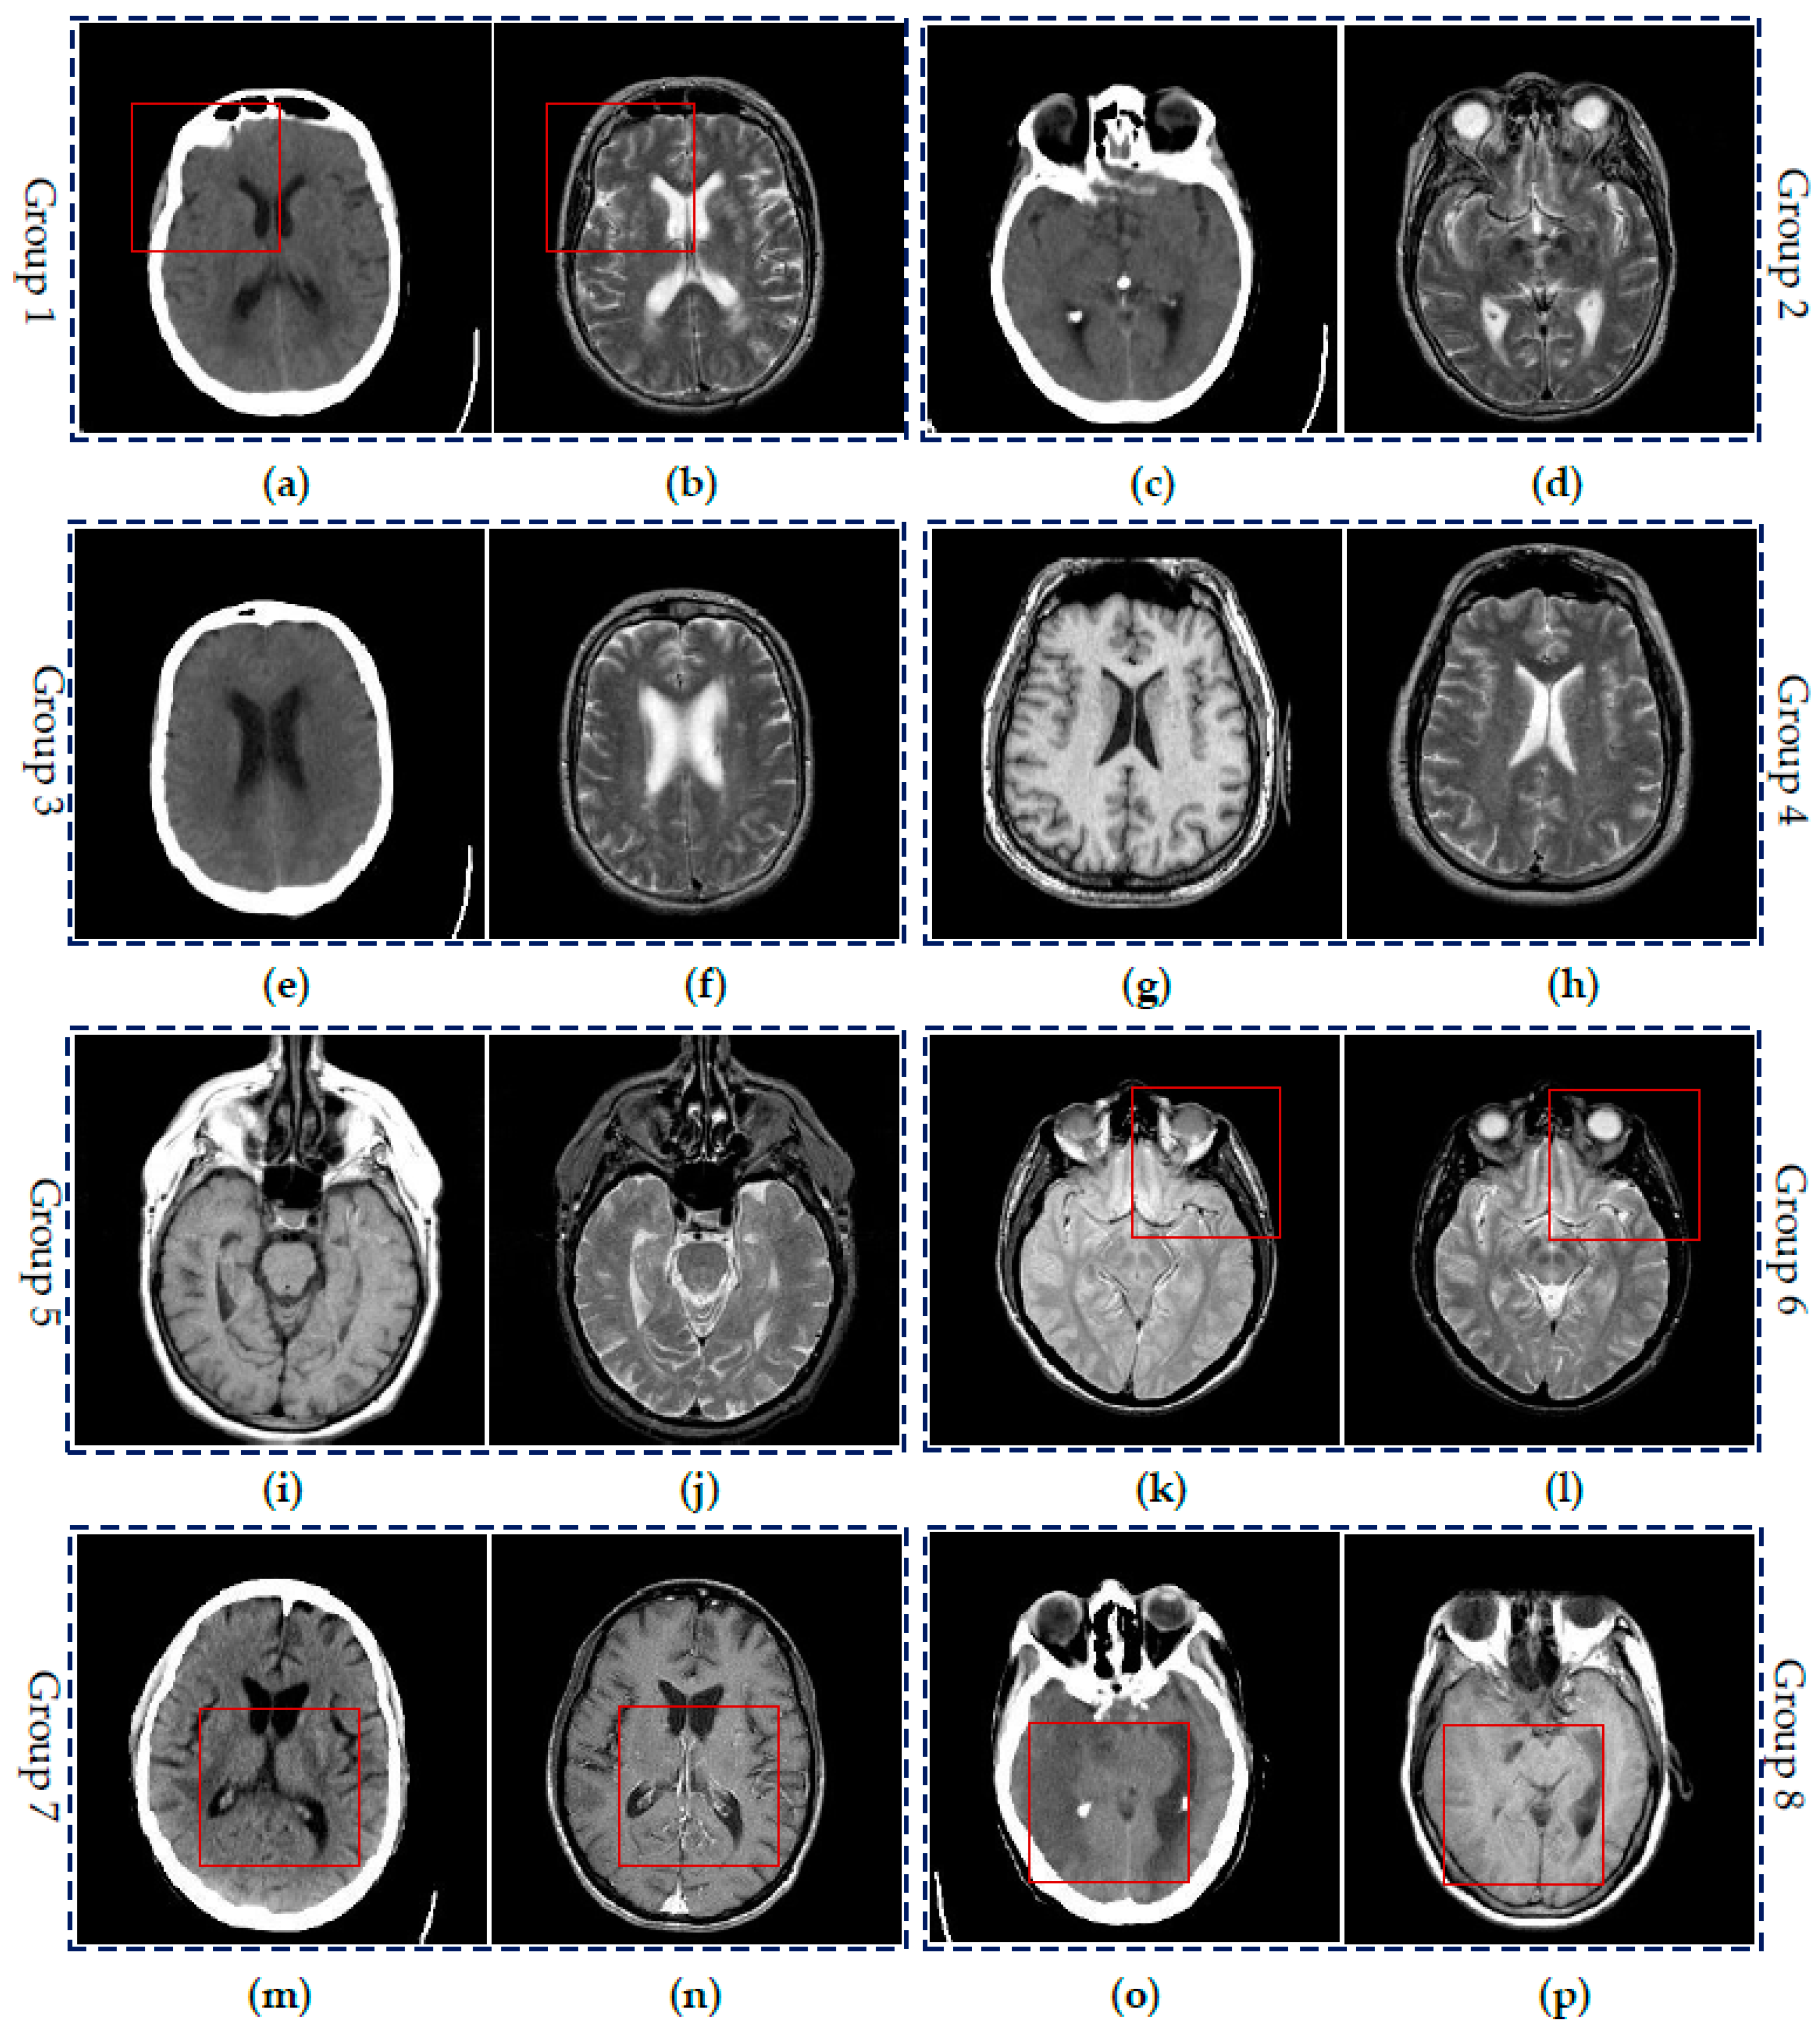

To demonstrate the effectiveness of the proposed SCM-M method, extensive experiments have been done on eight groups of CT and MR images shown in Figure 6. All the images are chosen from the website [43]. Each image is of size 256 × 256. Two images in each image pair include the complementary information. Here, Groups 1–3 are three pairs of CT and MR images of different regions in the brain of a patient with acute stroke. Group 4 includes the transaxial MR images of the normal brain. Groups 5 and 6 are MR images of the brain of patients with vascular dementia and AIDS dementia, respectively. Groups 7 and 8 are two pairs of CT and MR images of the brain of the patients with cerebral toxoplasmosis and fatal stroke. Please note that intensity standardization and inhomogeneity correction have been performed on all MR images by the above website.

Figure 6.

Six groups of source medical images: (a,c,e,m,o) CT images; (b,d,f,h,j,l) MR-T2 images; (g,i,p) MR-T1 images; (k) MR-PD image; and (n) MR-GAD image.